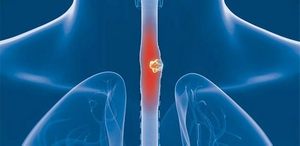

Диагностические процедуры

Первостепенное значение имеет осмотр больного и сбор анамнеза. Врач тщательно осматривает глотку, гортань и шейную область пациента, затем назначает рентгенограмму пищевода (подробнее о ней) и эзофагоскопию.

Благодаря этим методам диагностики, можно детально исследовать целостность эзофагеальной стенки и слизистой оболочки пищеводного канала, а также глубину поражения и степень осложнения патологического процесса.